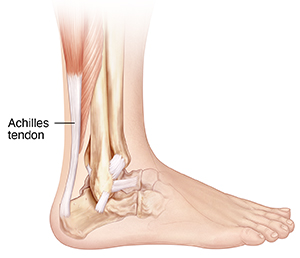

Understanding Achilles Tendonitis

Achilles tendonitis is an overuse injury. It causes inflammation of the Achilles tendon. This tendon is found on the back of the ankle. It links the calf muscle to the heel bone. It helps you do pushing-off movements like running or standing on your toes.